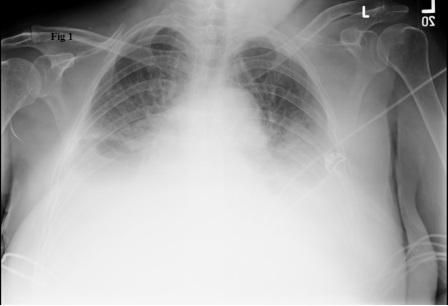

A 73-year-old woman was admitted with a 1-week history of worsening shortness of breath and bleeding from a new left breast mass. She had a history of hypertension and type 2 diabetes mellitus. She was afebrile, hypertensive, tachycardic, and dyspneic on rest.

A breast examination showed an ulcerated and necrotic mass in the left breast that involved the nipple. There were multiple palpable, hard and fixed lymph nodes in the bilateral axillae and supraclavicular areas. There was dullness to percussion over both sides of the chest posteriorly.

A chest radiograph showed moderate to large bilateral pleural effusions. A new chest radiograph showed diffuse infiltrates over bilateral lower lung fields, consistent with re-expansion pulmonary edema (REPE), a type of noncardiogenic pulmonary edema that follows re-expansion of the lung after performing thoracentesis for large amounts of pleural effusion or pneumothorax.

Pathophysiologic mechanisms include increased permeability of the pulmonary capillaries resulting from inflammation, increased pulmonary hydrostatic pressure caused by enhanced venous return, altered lymphatic clearance, and decreased amounts of functional surfactant. Clinical features of REPE include chest discomfort, persistent cough, tachypnea, tachycardia, and worsening hypoxemia that may be refractory to oxygen therapy. Diagnosis usually is based on the characteristic serial radiographic features.